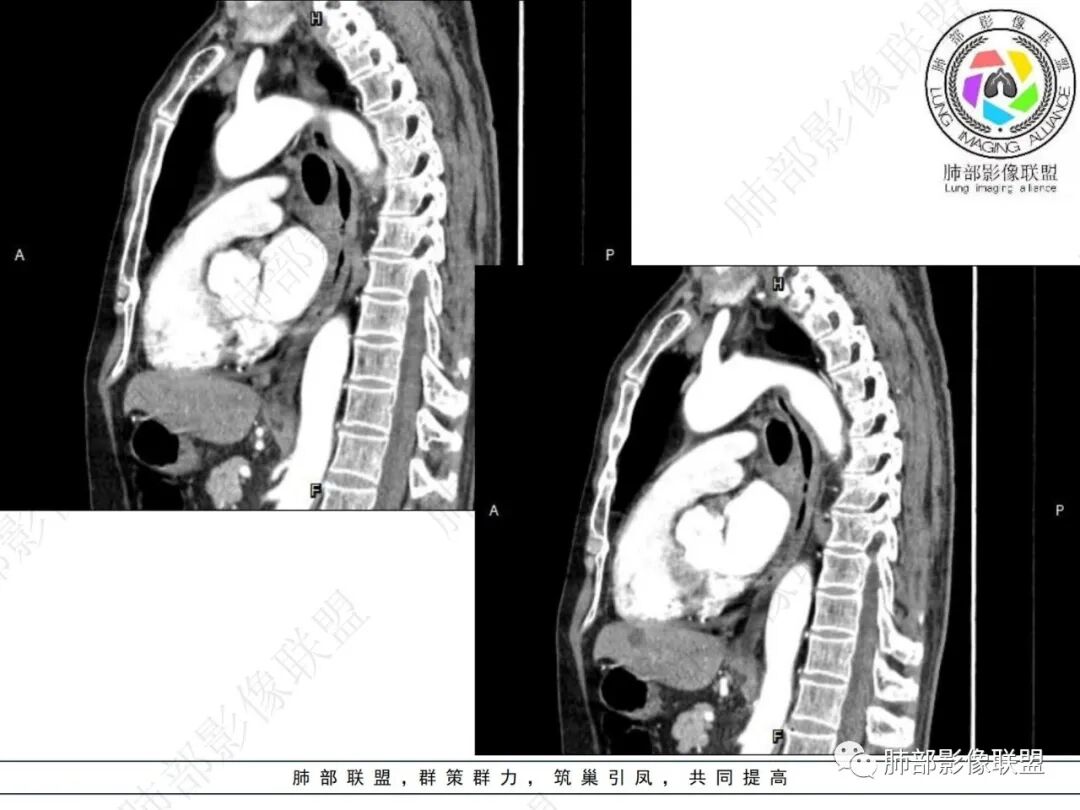

右肺下叶沿肺叶肺段分布斑片、条片状影,以下叶背段为显,边缘模糊,内可见支气管走行,局部支气管管壁增厚,右侧胸腔少量积液。纵隔隆突下可见不均匀软组织密度影,与周围结构分界不清,内见气体密度影,与食管及相邻右肺支气管之间未显示通道。邻近食管下段壁明显不规则增厚,增强后食管管壁明显不均匀强化,可见线样强化的连续完整粘膜影。

3.综合分析:

右肺下叶片影,气道相关,符合感染性病变。纵隔隆突下软组织密度影,异常气体影,长病程,起病缓慢,提示存在气管或食管瘘。食管镜未见明显新生物形成,临床未提供进食或饮水呛咳临床表现,综合分析应该考虑支气管瘘的形成。

对比患者3月份的CT图,原隆突下存在增大钙化淋巴结,现在出现气体影,且钙化显示不清,应想到淋巴结结核破溃成瘘可能性。

追溯寻找既往影像资料对影像诊断也至关重要。该病灶因毗邻食管,临床工作中还有详细询问患者的吞咽情况,是否存在呛咳、呕吐情况,及与呼吸道发病时间的先后顺序。

应当注意的是,瘘口较小或较为隐匿时,内窥镜寻找并非易事,影像检查使用阳性对比剂,或者临床使用美兰等有助于确立判断。